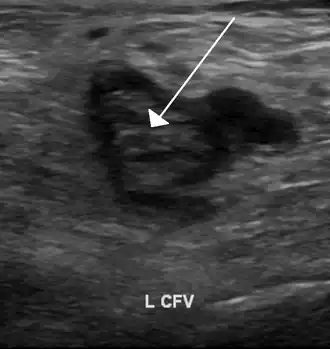

Compression ultrasonography for suspected deep vein thrombosis is the standard diagnostic method, and it is highly sensitive for detecting an initial DVT.[118] A compression ultrasound is considered positive when the vein walls of normally compressible veins do not collapse under gentle pressure.[39] Clot visualization is sometimes possible, but is not required.[119] Three compression ultrasound scanning techniques can be used, with two of the three methods requiring a second ultrasound some days later to rule out the diagnosis.[118] Whole-leg ultrasound is the option that does not require a repeat ultrasound,[118] but proximal compression ultrasound is frequently used because distal DVT is only rarely clinically significant.[117] Ultrasound methods including duplex and color flow Doppler can be used to further characterize the clot[117] and Doppler ultrasound is especially helpful in the non-compressible iliac veins.[119]

An ultrasound with a blood clot visible in the left common femoral vein. (The common femoral vein is distal to the external iliac vein.)